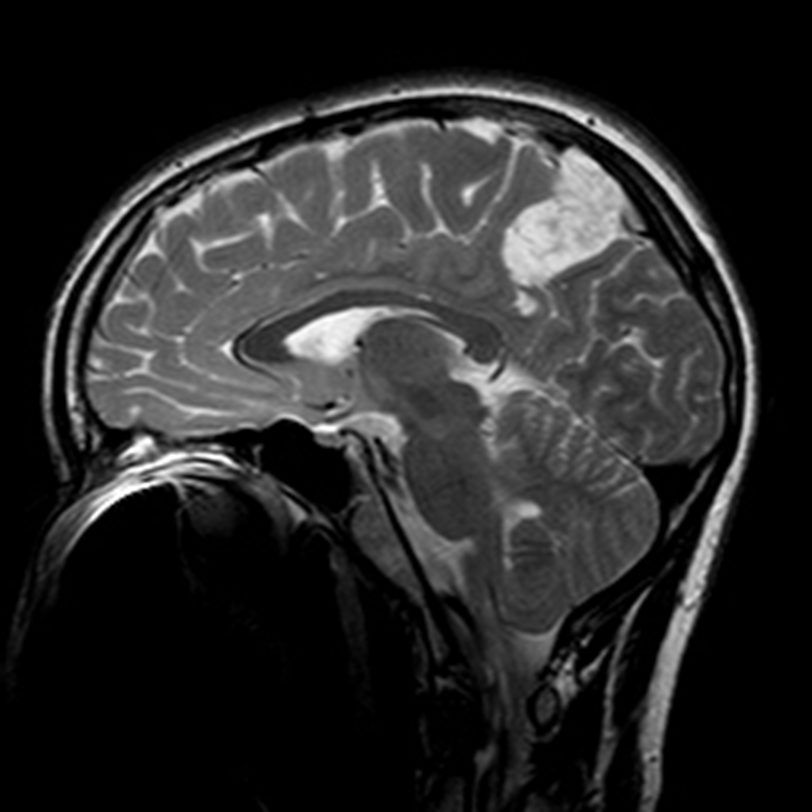

Found in white matter of young adults, 30-40 yrs

> 10 years survival

Astrocytoma WHO grade 2

T2-bright but lacks contrast enhancement

Prognostic factors: patient age, extent of resection, neurological status at presentation

Astrocytoma, WHO grade II

Diffuse enhancement gray and white matter

May remain stable for many years or undergo anaplastic transformation

Diffuse Astrocytoma, WHO Grade II